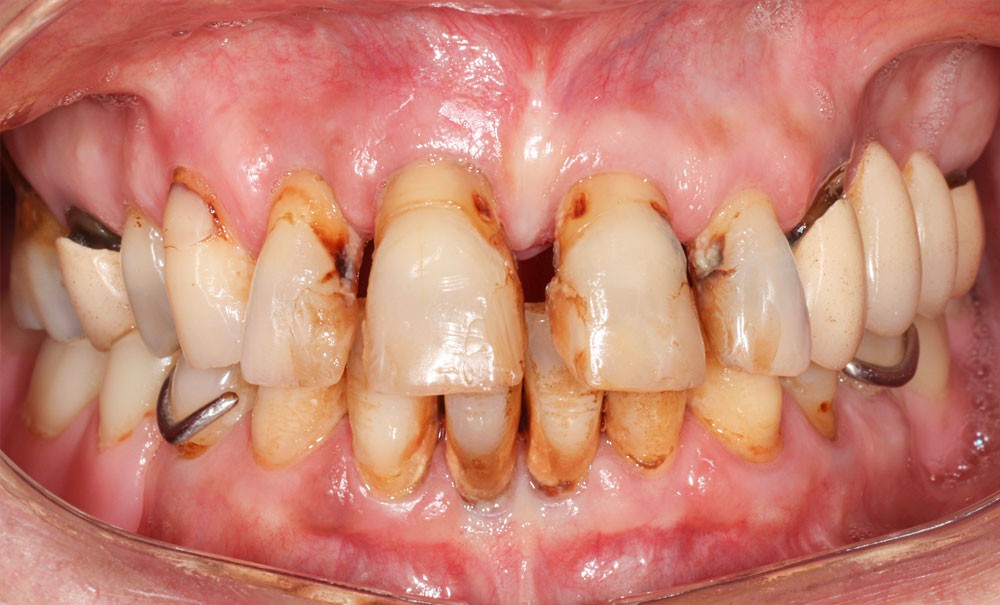

Qu’est-ce qu’une parodontite stade IV grade C selon Chicago 2017 ?

Il s’agit d’une parodontite sévère à progression rapide avec perte potentielle de toute la denture [1].

Le stade IV est caractérisé par :

- une perte d’attache clinique (CAL)* interdentaire ≥ 5 mm (dans le site le plus atteint et sur au moins 2 dents non adjacentes) ;

- une perte osseuse radiographique** ≥ 50 % du support osseux initial avec une alvéolyse verticale ≥ 3 mm ;

- un nombre de dents perdues pour raison parodontale ≥ 5 ;

- une profondeur de poche ≥ 6 mm ;

- la présence de lésions inter-radiculaires de classe II ou III ;

- un défaut crestal sévère ;

- un besoin de réhabilitation complexe.